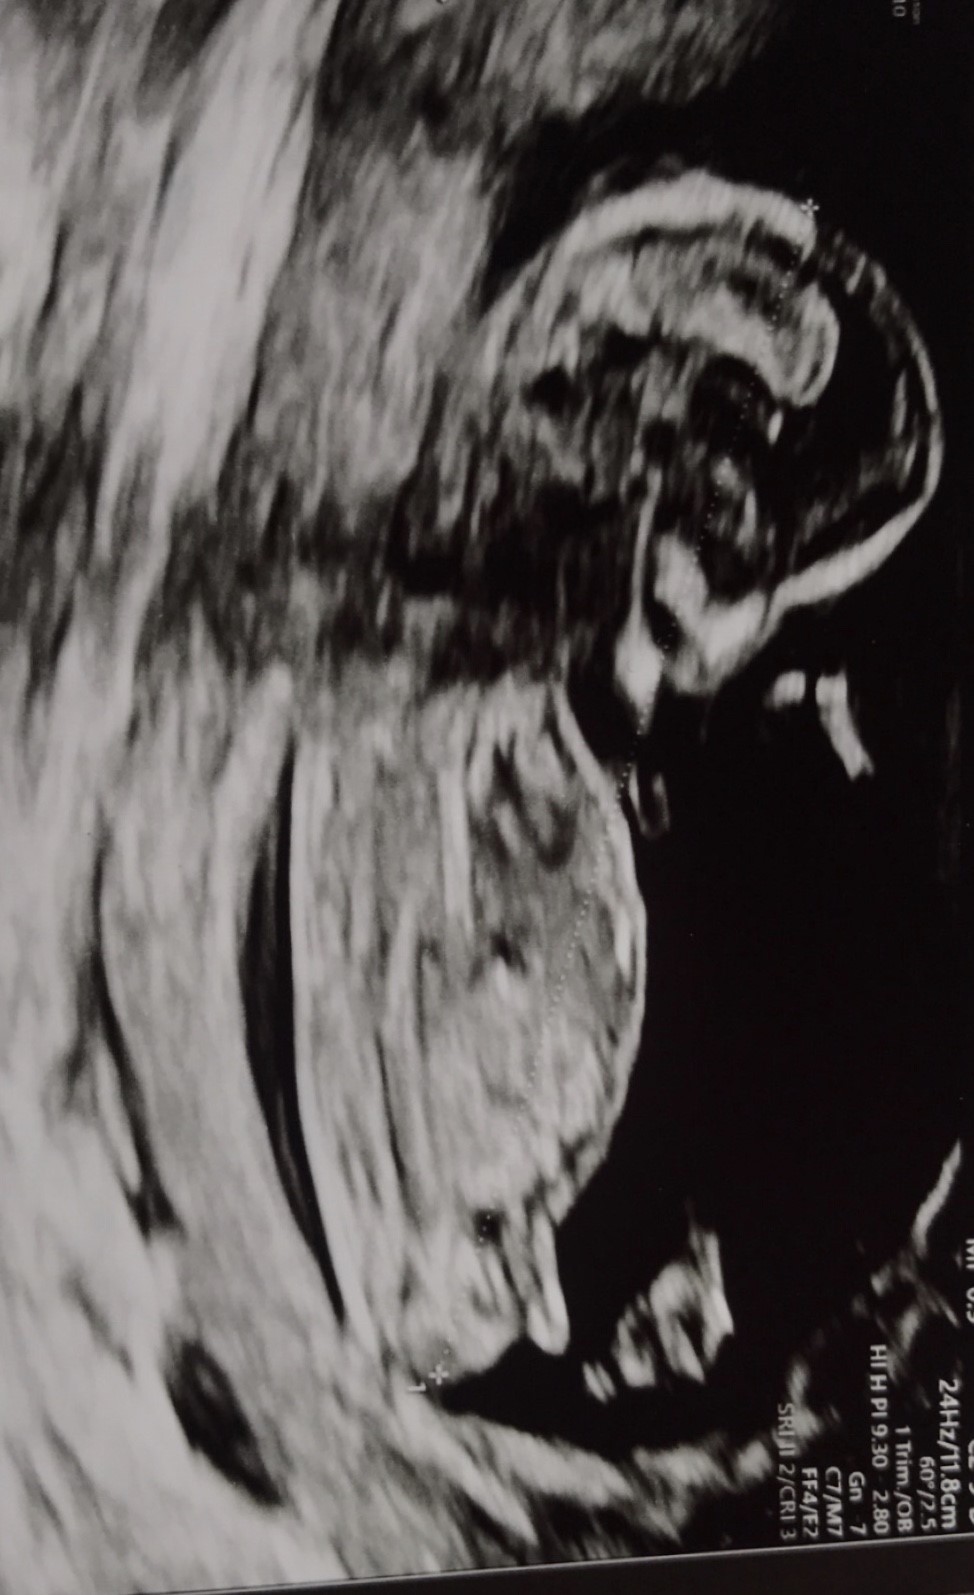

Jeg var til nakkefold i går og er 13+2. Er der nogen, som via nubben kan se, om det evt er en dreng eller pige?

Jeg gætter på pige

Gætter også på pige

Det ligner en pige :-)

Det er en tydelig pige nub